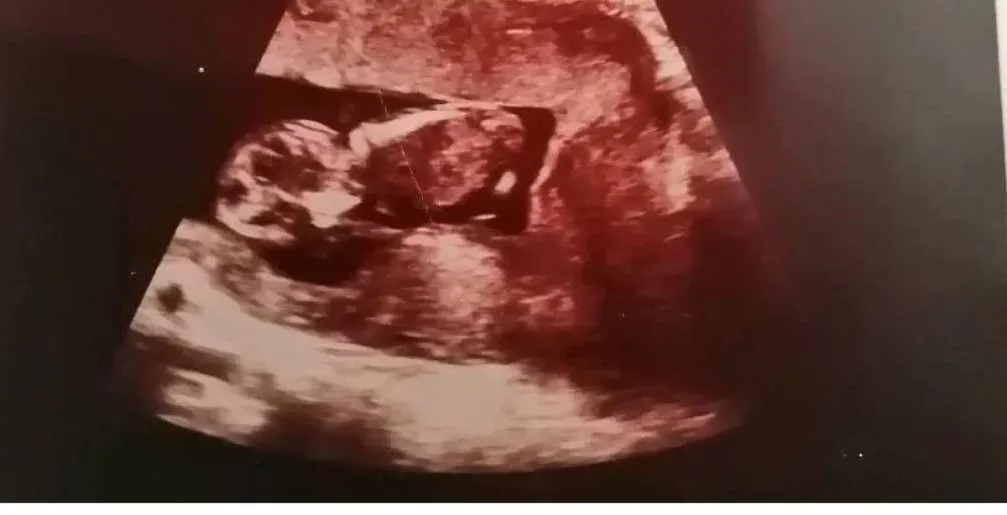

Andrea és párja hatalmas várakozással készült első közös gyermekük Istvánka megszületésére, ám a boldog tündérmese egyik pillanatról a másikra tragédiába fordult. Andrea terhessége zavartalan volt, ám a fájások beindulásával az izgatottságot félelemmel vegyes érzések váltották fel, ugyanis a szülés korai szakaszában komplikáció lépett fel. A súlyos vérveszteség ellenére Andrea képes volt megszülni gyermekét, ám miután magához tért orvosai közölték vele a felfoghatatlan hírt: Istvánka halva született.